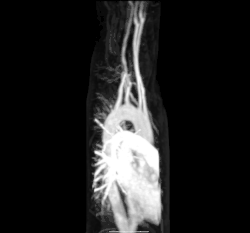

Magnetic resonance angiography of aberrant subclavian artery

Other more invasive means can also be used. A cannula or catheter inserted into an artery may be used to measure pulse pressure or pulmonary wedge pressures. Angiography, which involves injecting a dye into an artery to visualise an arterial tree, can be used in the heart (coronary angiography) or brain. At the same time as the arteries are visualised, blockages or narrowings may be fixed through the insertion of stents, and active bleeds may be managed by the insertion of coils. An MRI may be used to image arteries, called an MRI angiogram. For evaluation of the blood supply to the lungs a CT pulmonary angiogram may be used. Vascular ultrasonography may be used to investigate vascular diseases affecting the venous system and the arterial system including the diagnosis of stenosis, thrombosis or venous insufficiency. An intravascular ultrasound using a catheter is also an option.